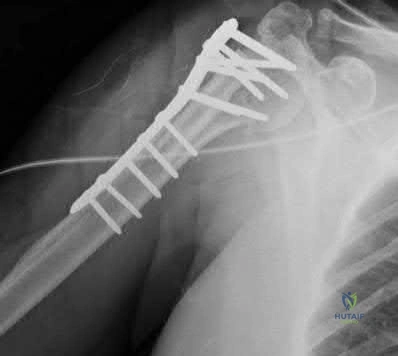

A 32-year-old female presents with a highly unstable, vertically oriented (Pauwels type III) femoral neck fracture following a fall from height. What is the most biomechanically advantageous construct for internal fixation of this specific fracture pattern to minimize shear forces?

Explanation